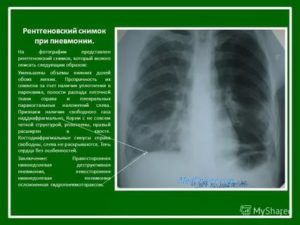

Рентгенограмма легких при пневмонии является классическим проявлением патологии. Приводим пример снимка при воспалительных изменениях легочной ткани (пневмония), чтобы читатели понимали, чем отличается норма от патологии.

Предлагаем ознакомиться с нижеприведенными снимками при пневмонии и в норме. Ответьте на вопрос, где рентгенограмма нормальная, а какая патологическая. Определите, на какой рентгенограмме пневмония.

Подскажем, что затемнение небольшое и локализовано над диафрагмой.

На представленной рентгенограмме лёгких визуализируется инфильтративная тень в наддиафрагмальной зоне слева. Корни тяжисты. Реберно-диафрагмальные синусы не завуалированы. Сердечная тень классической конфигурации. Патологии в мягких тканях не прослеживается.

Заключение: Рентген признаки левосторонней сегментарной пневмонии. Рекомендована рентгенография органов грудной клетки в левой боковой проекции для установки локализации затемнения.